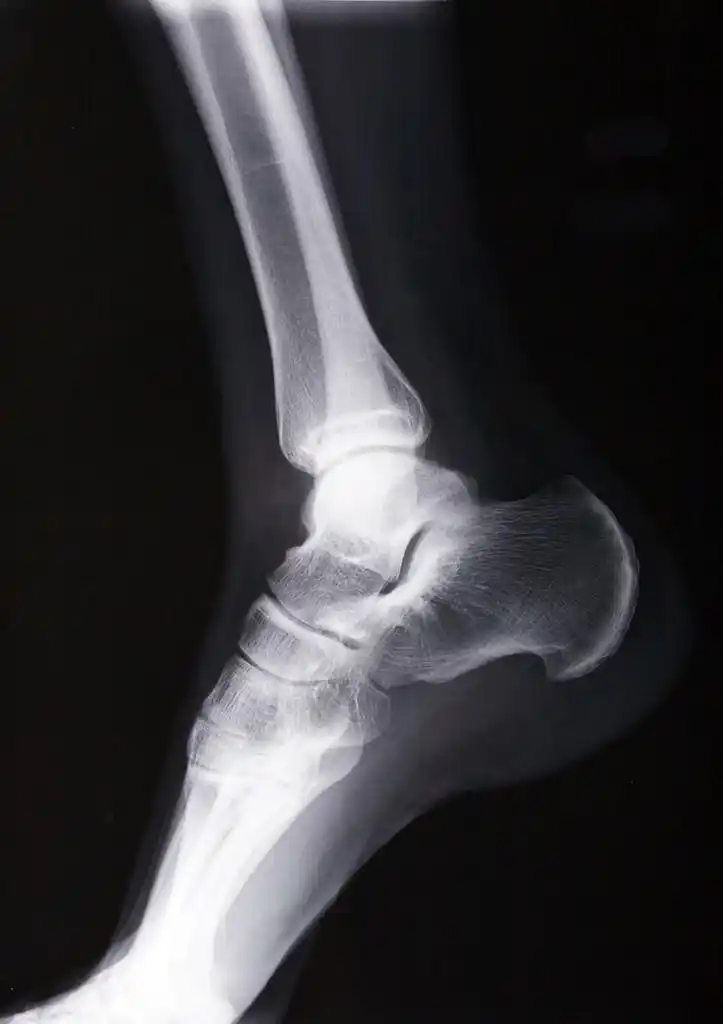

踝关节正侧位

踝关节,正位和侧位x线照片

请骨科战友帮忙看一下左踝关节x线片 [病例帖]

与胫骨,腓骨相 交于a,b,c,d四个点 ,踝穴宽度=ab-cd ,正常范围2~6mm